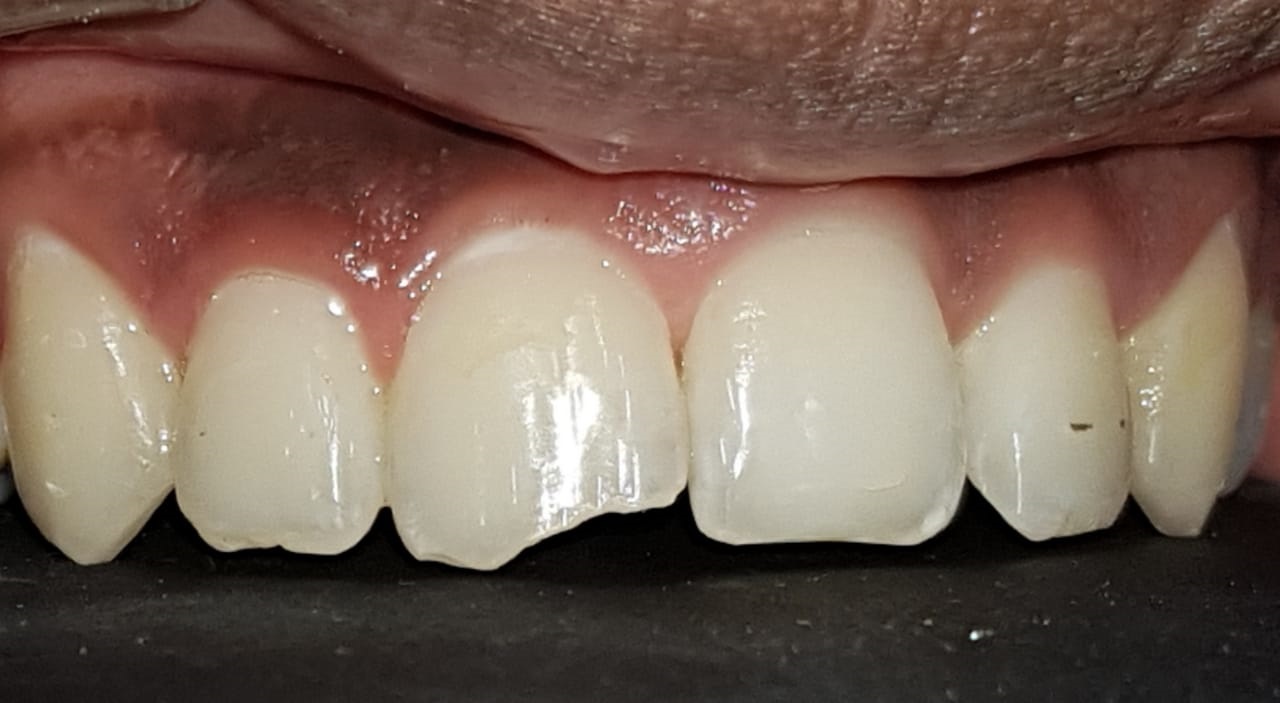

समोरचे दात जर किडलेले असतील तर त्यामध्ये दातांच्या रंगाचे फिलिंग (कंपोझिट) करता येते. खूपच किडलेल्या दातांना रूट कॅनाल ट्रीटमेंट करून, अगदी हुबेहूब नैसर्गिक दिसणारे सिरामिक किंवा झिरर्कॉनियम चे दातही बसविता येतात .

We do Composite( tooth colored )fillings, Laminates, veneers, Thineers, Laminates etc.

Prosthodontics refers to the replacement of missing teeth. Crowns and bridges are placed. made up of metail or ceramic,designed to look exactly like natural teeth. Option such as zirconia, E-mac and Lava (5 to 15 years gurantee) are available as well as implants-the most contemporary way to replace single, multiple or all teeth.

From subtle changes to major repairs, we can perform a variety of procedures to improve your smile. There are many techniques and options to treat teeth that are discolored, chipped, misshapen or missing the dentist can reshape your teeth, close spaces, restore worn or short teeth or alter the length of your teeth. Common procedures include bleaching, bonding, caps, crowns, veneers, and reshaping and contouring.